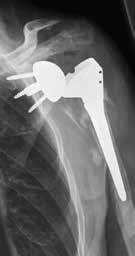

Weltweit werden die meisten Schulterprothesen von Operateuren implantiert, die weniger als zehn Implantationen pro Jahr durchführen 1. Das bringt die Gefahr mit sich, dass sich die Zahl der Komplikationen erhöht. Die inverse Schulterprothetik führt durchaus zu einer guten Rekonstruktion der Funktion bei Patienten mit Rotatorenmanschettendefekten 2. Durch die Umkehrung von Konvexität am Glenoid und Konkavität am Humerus wird das Drehzentrum distalisiert und medialisiert, was zu einer Reduktion des Drehmoments und zu einem zusätzlichen Recruitment von Deltafasern führt (Abb. 1a u. b) 3.

Gleichzeitig entstehen jedoch Komplikationen wie Instabilitäten mit Luxation (Abb. 2), akromiale Frakturen sowie Lockerungen glenoidaler und humeraler Komponenten, die in dieser Art bei den bisherigen Prothesen nicht bekannt waren. Villacis et al. (2016) 4 untersuchten die Komplikationen nach Schultervollprothesen im Vergleich mit inversen Prothesen bei 10.844 Prothesen. Die Komplikationsrate bezüglich Infektion und Dislokation war unterschiedlich zu Ungunsten der inversen Prothesen.